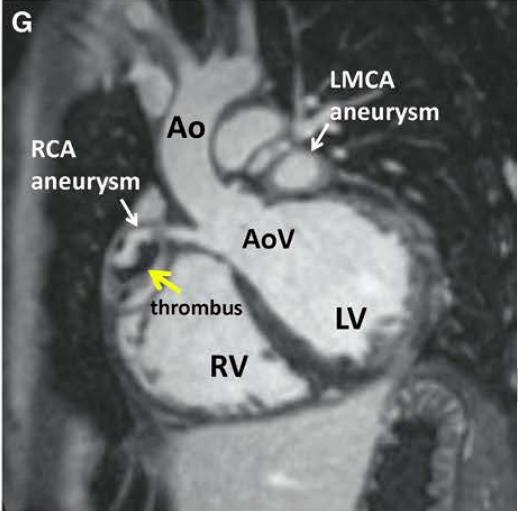

磁共振呈像,白色箭头所指冠状动脉瘤,参考1

川崎病的主要并发症为冠状动脉异常(CAA),CAA可能导致心肌缺血、心肌梗死和猝死。通常最先通过超声心动图发现。CAA的分类依据是Z值(根据体表面积校正的冠状动脉内径)。

CAA位于心外膜冠状动脉,最常见于左前降支近端和右冠状动脉近端。按发生频率依次为:左冠状动脉主干、冠状动脉回旋支、右冠状动脉远端,以及冠状动脉后降支在右冠状动脉上的起始处。CAA好发于分支处,这提示了剪切应力的病理学作用。

建议所有的川崎病患者应行:超声心动图、心电图检查。如果超声心动图不能充分显示冠状动脉,则使用超高速计算机断层扫描血管造影(computed tomographic angiography, CTA)、磁共振血管成像(magnetic resonance angiography, MRA)充分呈现冠状动脉树。